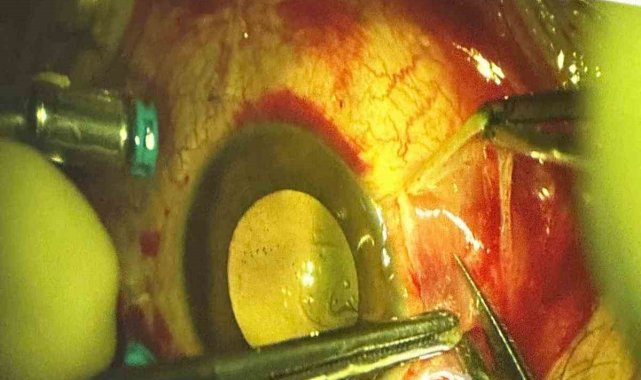

"Müvekkilim ile eşi bir süredir ayrı yaşıyor. Müvekkilim, eşinin talebi üzerine evde unuttuğu özel eşyayı kayınpederinin evine götürüyor. Aracında eşini beklerken kayınpederi elindeki tüfekle araca ateş ediyor. Saçmalar hem araca hem müvekkilime isabet ediyor. Şu ana kadar dört operasyon geçirmesine rağmen görmesinde bir iyileşme sağlanamadı. Göz nakli gerekebilir. Araçta yaklaşık 20 saçma izi var. Müvekkilimin gözünde, kulağında ve başında saçmalar bulunuyor."